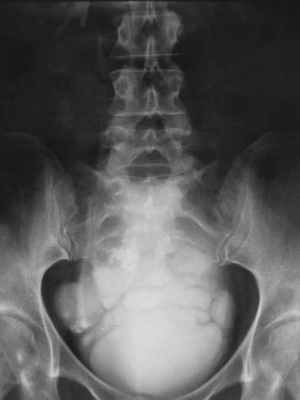

Диагноз устанавливается на основании УЗИ (рис. 5.35), цистографии (рис. 5.36) и цистоскопии (рис. 20, см. цв. вклейку).

Рис. 5.36. Нисходящая цистограмма. Дивертикулы мочевого пузыря